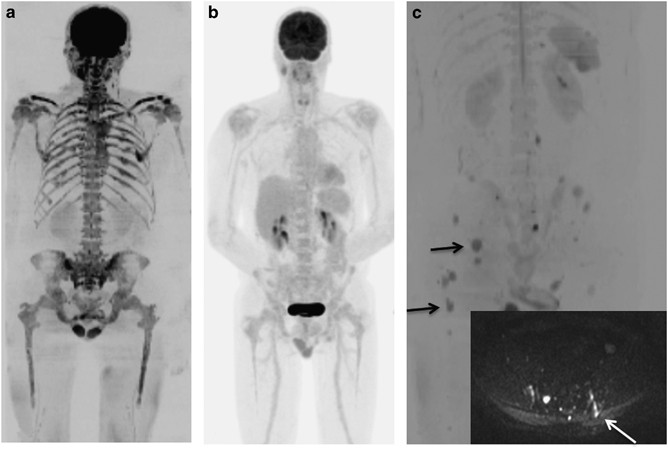

Diffuse disease was reported in 37% (51/138) of regions imaged on WB-DWI scans compared with only 7% (10/140) on FDG PET–CT (2 regions in 1 patient were not included in the DWI scan). The regions reported as having diffuse disease on WB-DWI were reported on FDG PET–CT as ‘no disease’ for most (36/51) regions (Figures 1a and b). Overall 3 patients were reported as being disease free on FDG PET–CT while having extensive (⩾3/7 regions) diffuse disease evident on WB-DWI, that is, representing a false-negative misdiagnosis by FDG PET–CT. These data demonstrate the clinically relevant superior sensitivity of WB-DWI in detecting the presence of diffuse disease over FDG PET–CT. To compare the ability of both modalities to detect focal lesions alone, whole-body scores were reanalyzed excluding diffuse disease. Mean scores for WB-DWI remained higher than for FDG PET–CT but this was not statistically significant, indicating at least equal sensitivity of WB-DWI for detection of focal lesions. (WB-DWI mean 7.45±10.32, FDG PET–CT mean 6.45±7.06, P=0.92).

WB-DWI improves detection of diffuse marrow infiltration compared with FDG PET–CT and detects trephine sampling error. WB-DWI b900 maximum intensity projection image (a) and FDG PET–CT (b) in the same patient. WB-DWI demonstrates diffuse infiltration of the bone marrow; FDG PET–CT shows no evidence of disease. WB-DWI b900 maximum intensity projection image (c) demonstrates multifocal disease (examples shown by arrows). Axial b900 image (superimposed) shows the trephine tract (arrow), which does not sample a focal lesion.

About 15/20 pairs had bone marrow trephines with adequate tissue for the calculation of PC% performed close to the FDG PET–CT and WB-DWI scans. The PC% was better correlated to WB-DWI scores (Spearman's r=0.36 95% confidence interval (CI) (−0.20, 0.74) P=0.19) than FDG PET–CT (Spearman's r=0.20 95% CI (−0.36, 0.67) P=0.46). In 93% of patients, the trephine PC% was similar to the qualitative WB-DWI report of activity at the iliac crests compared with only 67% for FDG PET–CT. Furthermore if the trephine preceded imaging, the tract was more readily visible on WB-DWI scans compared with FDG PET–CT scans (Figure 1c).